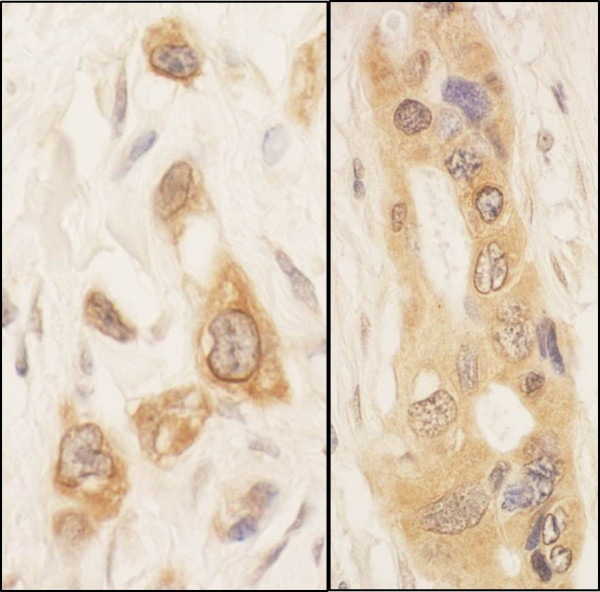

Product information "Anti-SPAK"

Protein function: May act as a mediator of stress-activated signals. Mediates the inhibiton of SLC4A4, SLC26A6 as well as CFTR activities by the WNK scaffolds, probably through phosphorylation. [The UniProt Consortium]

| Application: | WB, IP, IHC |

| Species reactivity: | human |

| Immunogen: | synthetic peptide. The epitope recognized by A302-465A-T maps to a region between residue 375 and 425 of human STE20/SPS1-related proline-alanine-rich protein kinase using the numbering given in entry AAC72238.1 (GeneID 27347). |